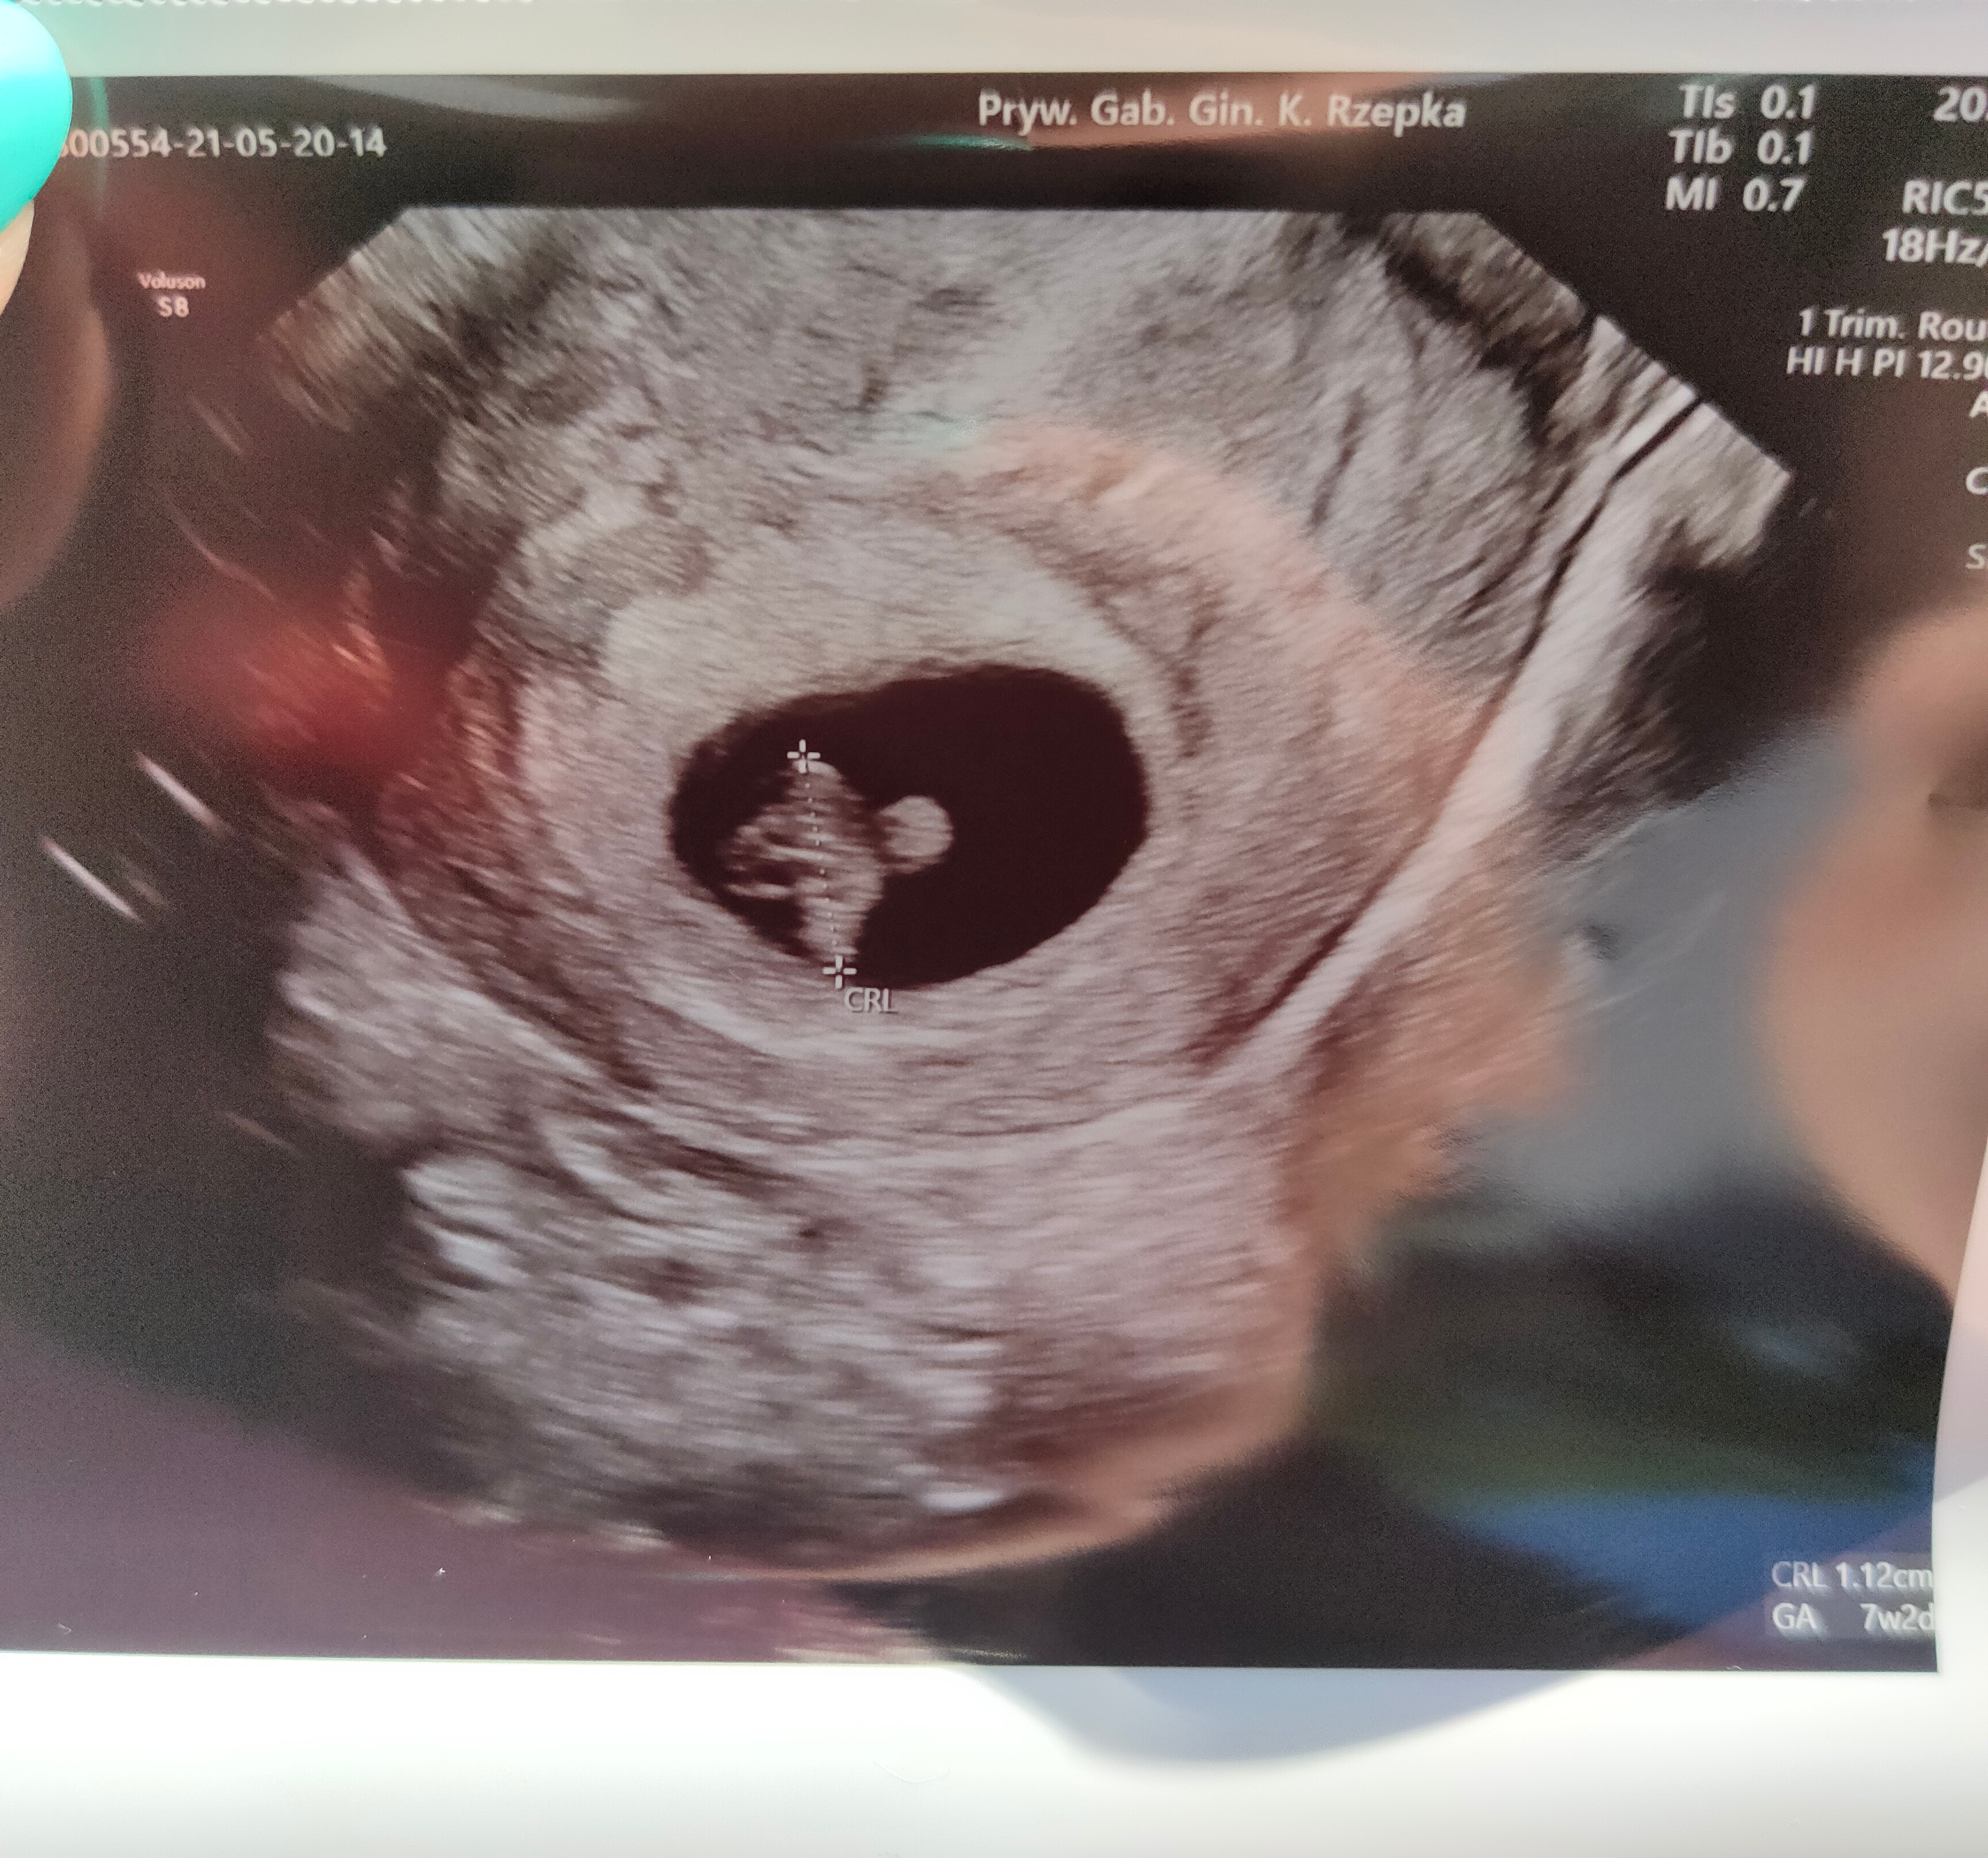

Dziewczyny powiedzcie mi ile razy miałyście już robione USG? Ja jestem w 7 tygodniu i miałam już 3 razy. W tym od razu słuchane było serduszko. Ja wiem że lekarz wie co robi, ale jednak..

Termin według OM to 09.01. To moja pierwsza ciąża![]()

Super gratulacje!!!! Który tydzień jesteś? Ale piekny fasol ❤❤❤No i jest fasolka, serduszko też pięknie bije. Co za radość![]()

No i jest fasolka, serduszko też pięknie bije. Co za radość![]()